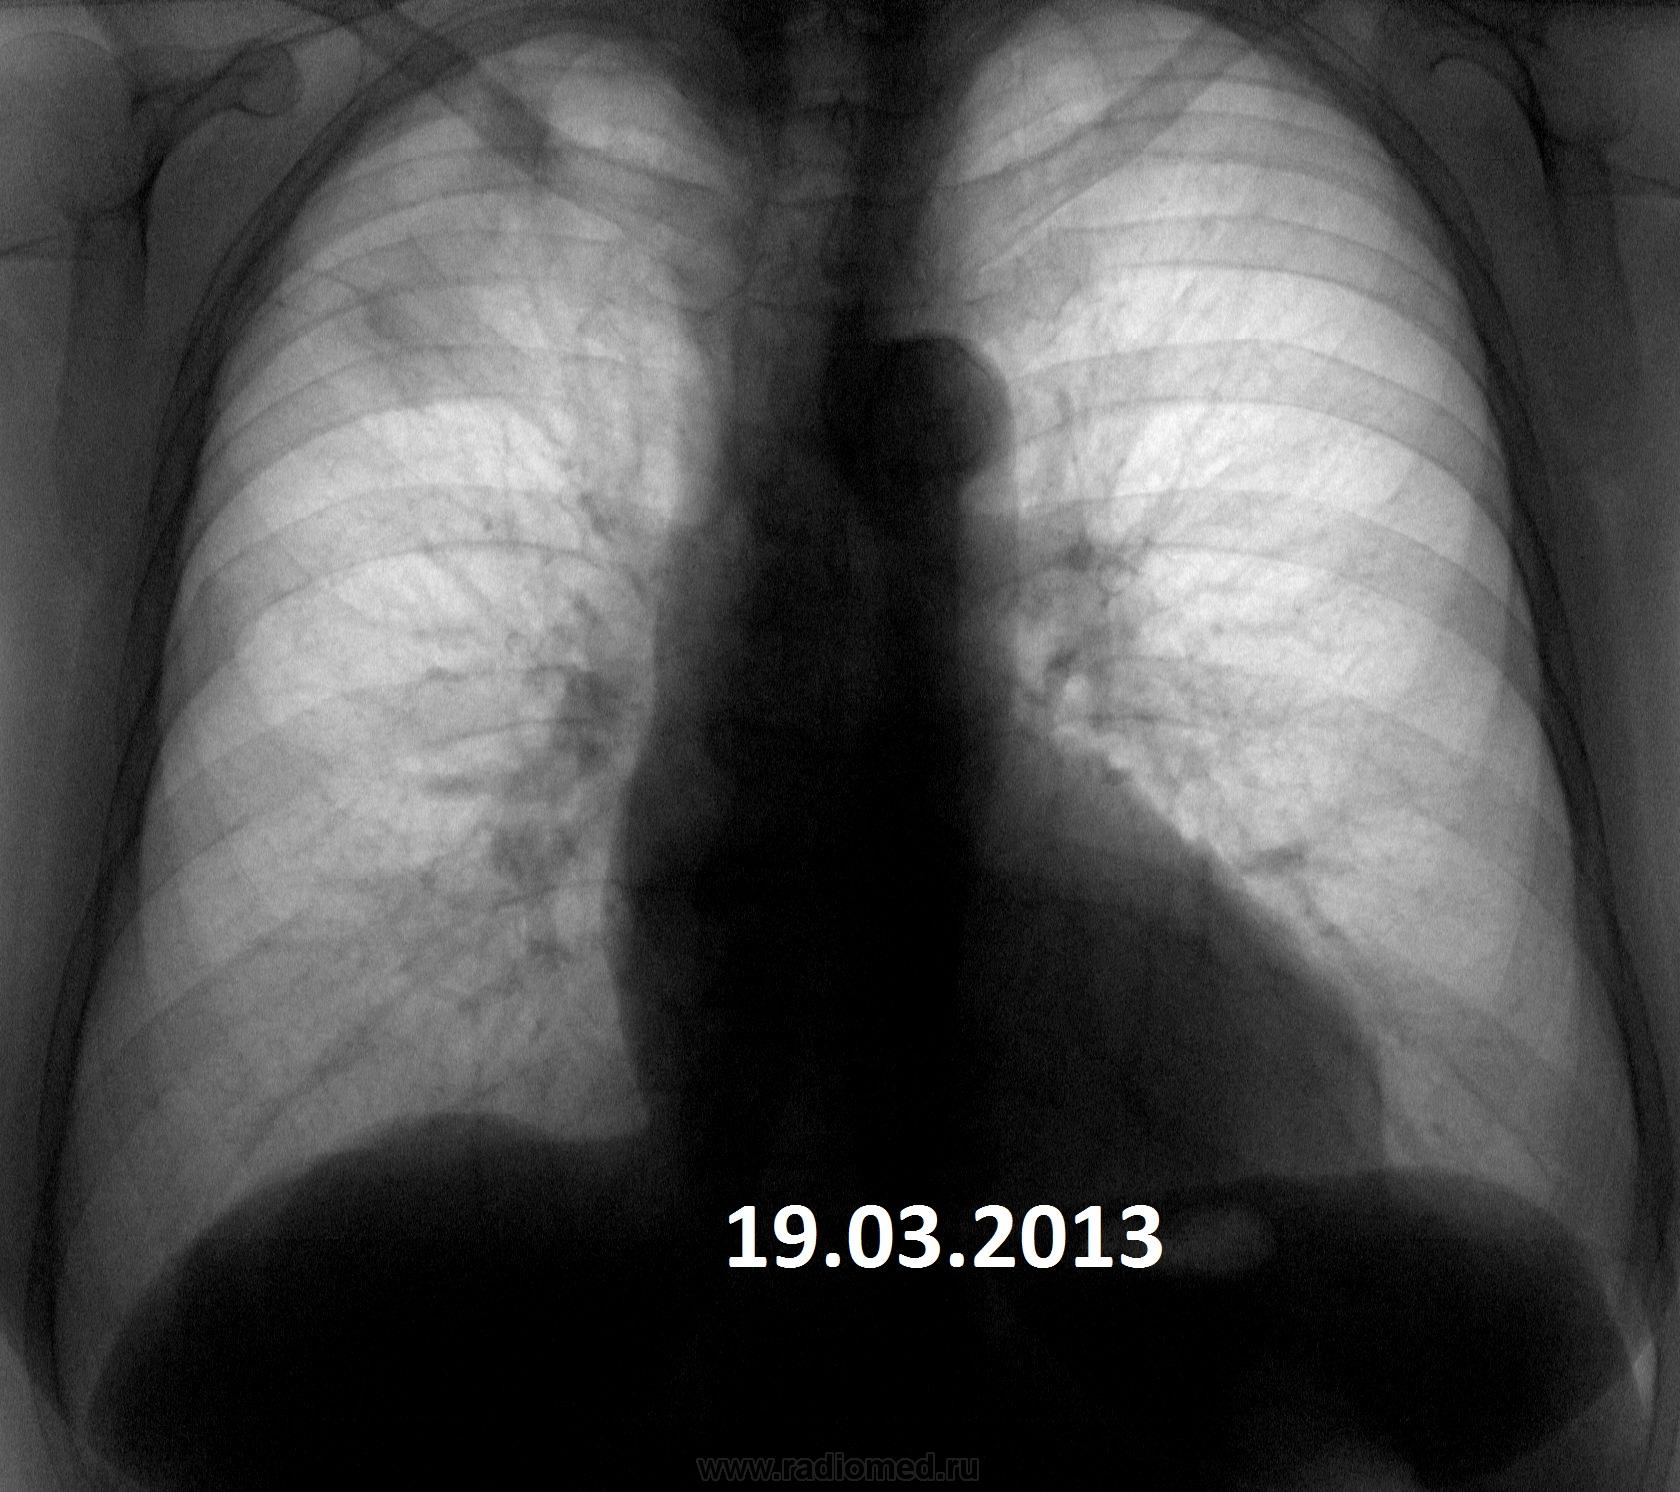

Пожилая опрятная женщина, жалоб нет, просит "отпустить". В феврале фтизиатры написали пневмонию. Сжалился - написал что-то вроде плеврофибрознотакая-то хрень.

• https://radiomed.ru/sites/default/files/styles/case_slider_image/public/user/3055/1937g.r.19.03.2013.jpg?itok=Pc9s_NW0

Коли фтизиатры отпустили так на них и грех.Сопоставляя с архивом от туберкулёза не отмахнёшся.

Но ведь не может туберкулез меделенно развиваться 4 года?

имеет место. Томографировать надо обязательно.

Не надо сбрасывать со счетов и левую верхушку.

Увы! Мне кажется - справа имеет место рецидив. Валентин Львович не зря на левую верхушку обратил внимание.

На первом месте- Tbc.

На втором: Если в легком неясная картина - ищи БАР.

В любом случае ТМГ.

+1. Не пневмония это точно. Прогресс слишком долгий. Больше склоняюсь к онко.

Я за онкологию